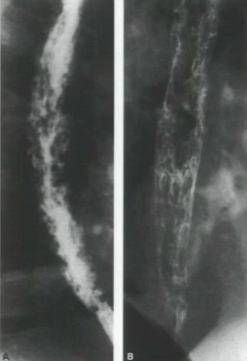

What is your diagnosis?

There is a mass blocking flow of the barium during the swallow indicating a filling defect. This is a large squamous cell carcinoma.

What could be causing the asymmetry seen on the right side of the image shown below?

It is a slight filling defect, it could be an early carcinoma.

What could be causing the sign shown below?

An advanced carcinoma. Note the multiple filling defects with ulcerations.